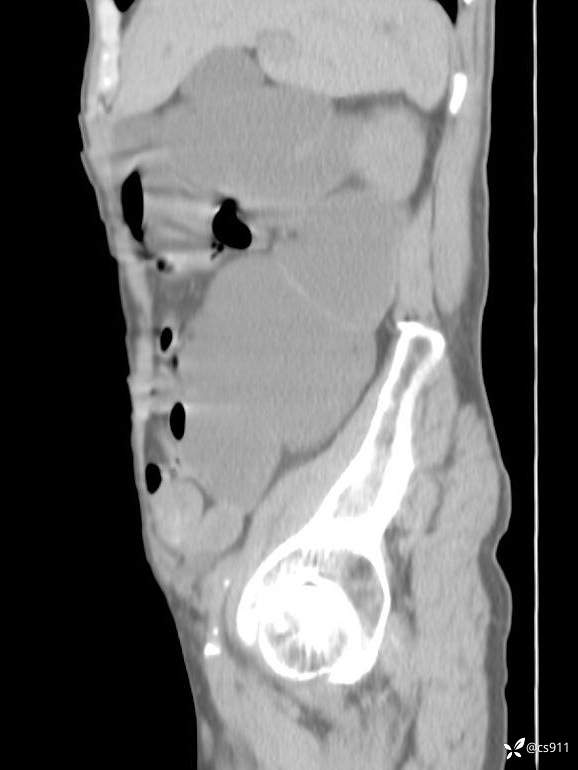

急腹症之急诊CT,原因?答案公布

男,77岁,腹痛、腹胀伴恶心呕吐1天。呕吐胃内容物,非喷射性呕吐,有咖啡色样胃内容物,诉有胃穿孔病史。查体:全腹平,下腹部压痛,全腹无反跳痛,叩诊呈浊音,移动性浊音阴性,肠鸣音减弱,1-2次/分。肛检:直肠未扪及明显肿物,可触及大量粪块。

T 36.6℃ P 80次/分 R 26次/分 BP 100/60mmHg

白细胞(WBC) H 14.55 10e9/L 4-10

中性粒细胞百分率(NEUT%) H 85.7 % 40-75

血淀粉酶(AMY) HH 1859 U/L 35-135

癌胚抗原(CEA) H 27.44 ng/ml 0-5

呕吐物 潜血试验 * 阳性 阴性

患者轮椅入室检查神志清楚, 能配合摆位和呼吸